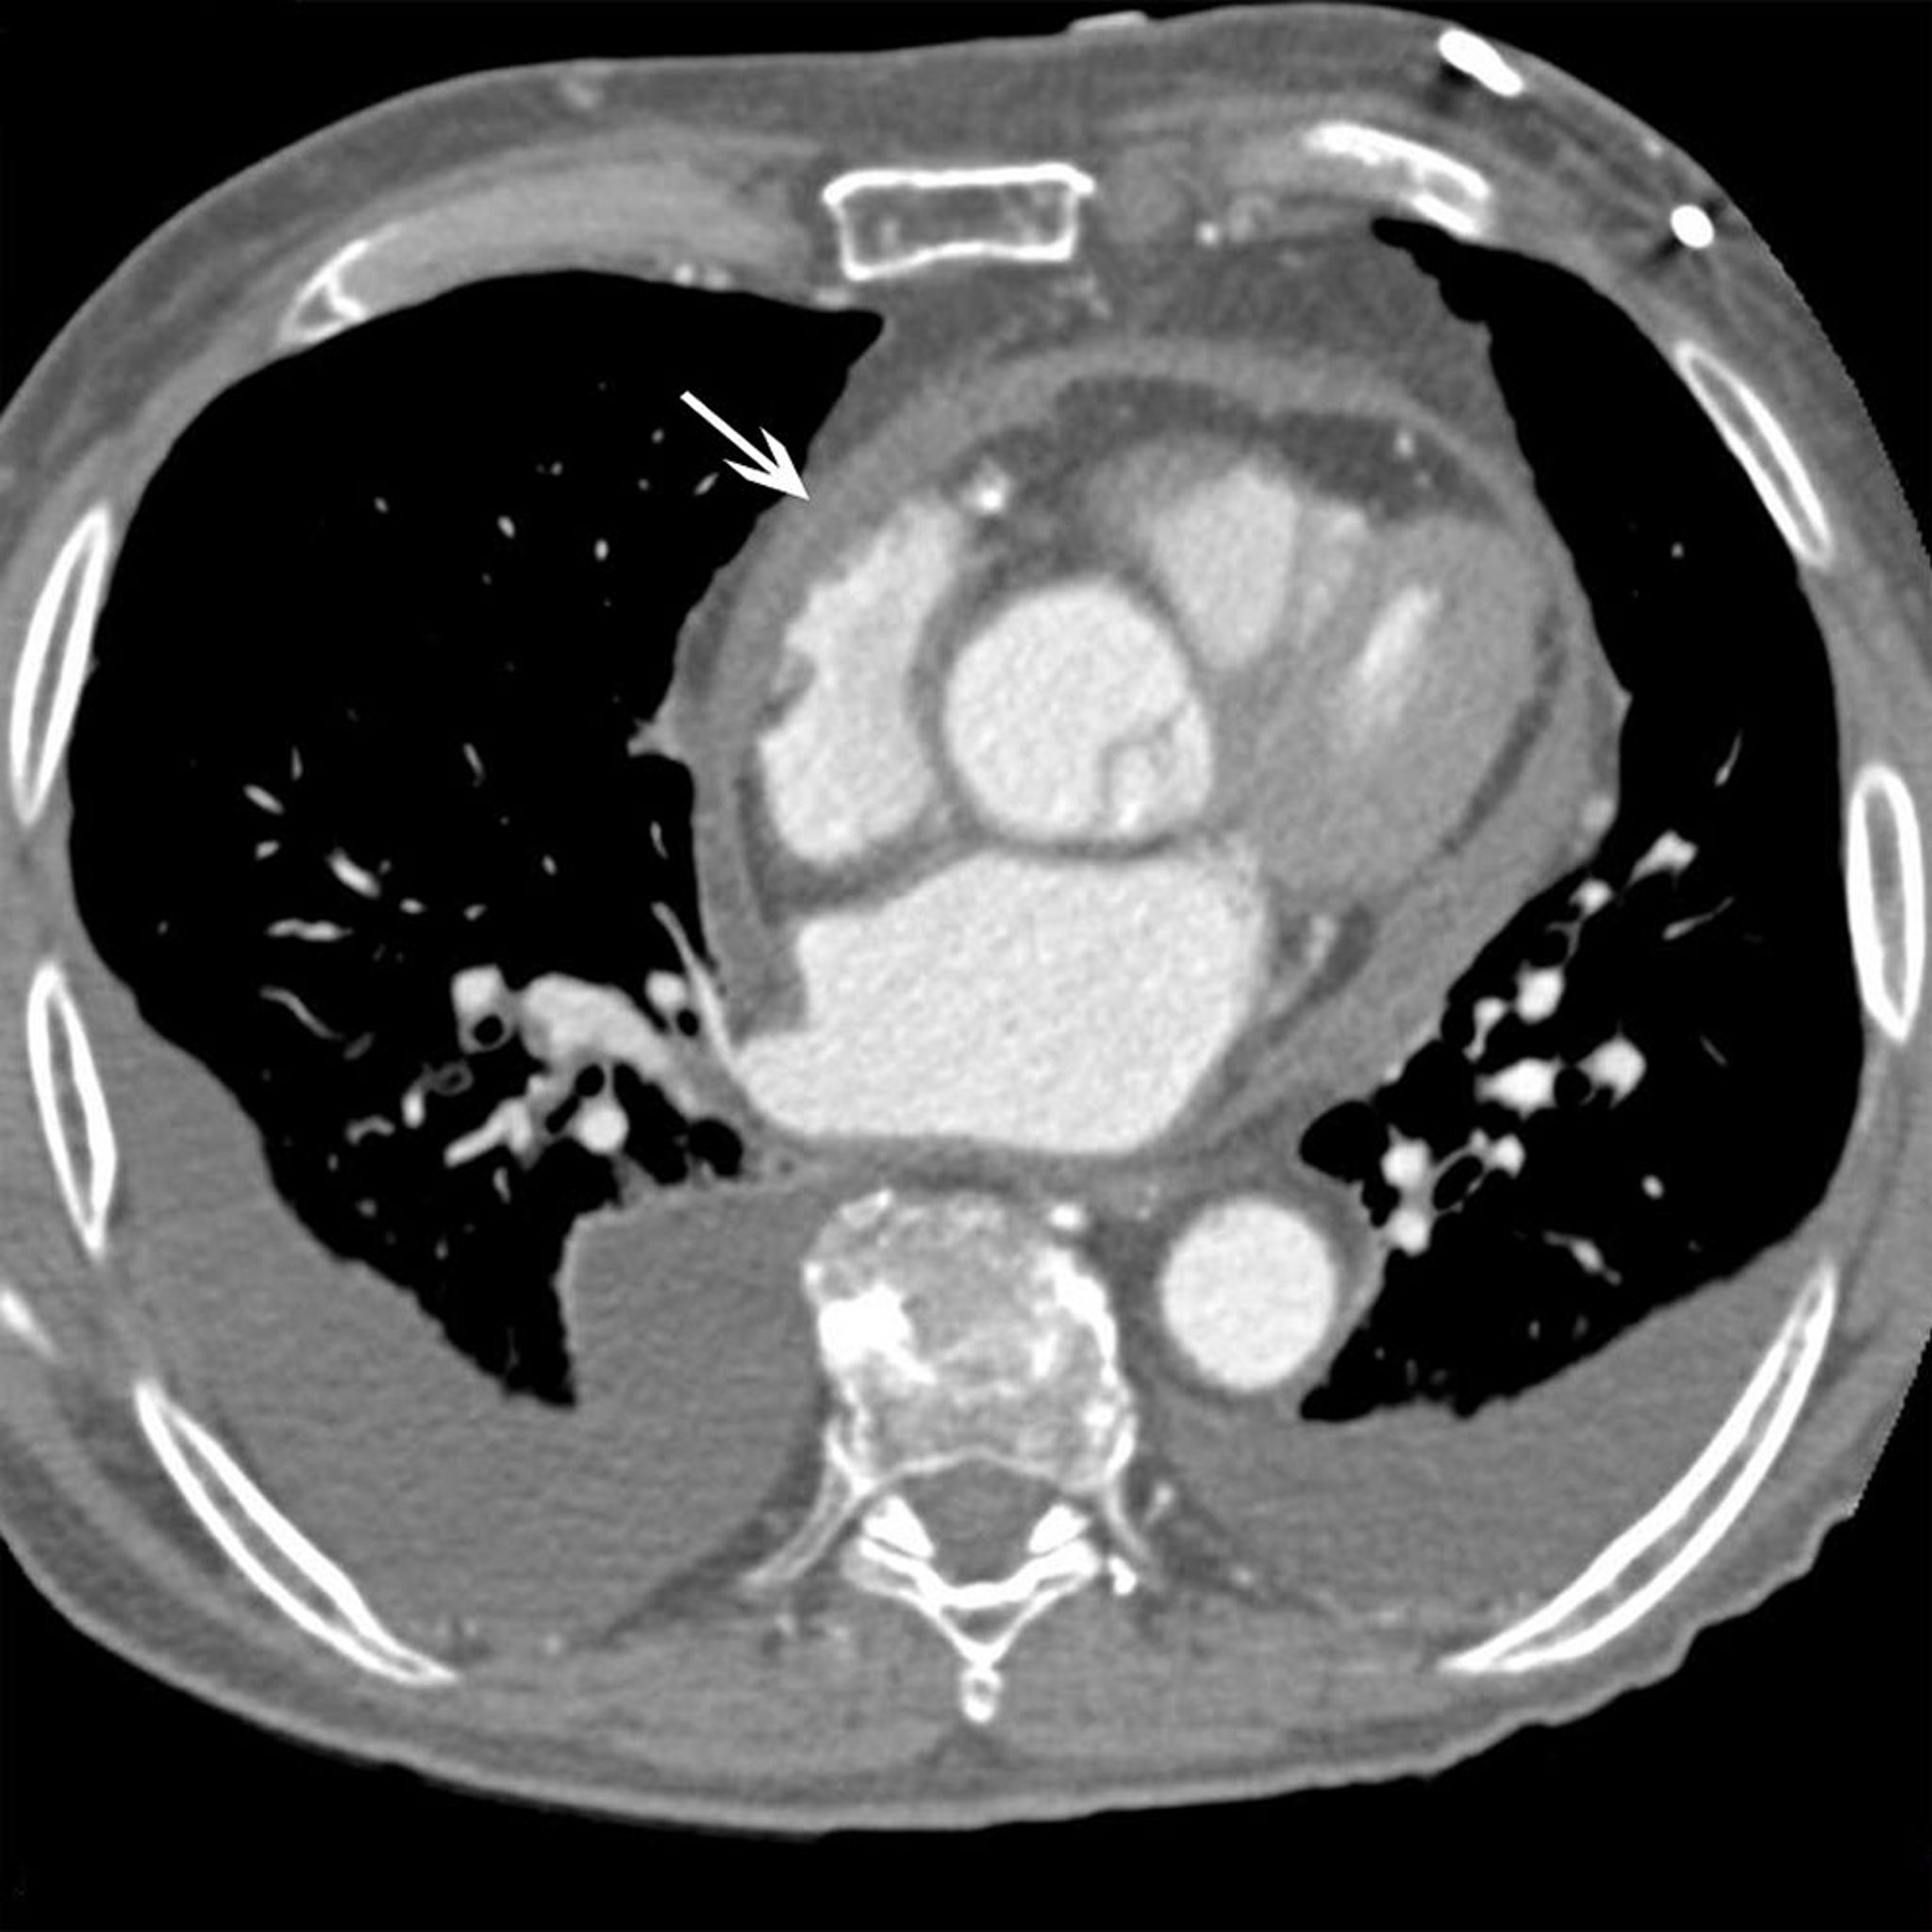

Although CT can detect a pericardial effusion (often incidentally on a scan done for other conditions), it may overestimate its size and is not a first-line test to evaluate possible pericardial effusion.

CT or MRI can identify pericardial thickening > 5 mm.

• Pericardial thickening > 4-mm, with typical hemodynamic changes (assessed by echocardiography and catheterization), can confirm constrictive pericarditis (2).

• When no pericardial thickening or fluid is seen, the diagnosis of restrictive cardiomyopathy is favored but not proved.

• A normal pericardial thickness does not exclude constrictive pericarditis.

CT or MRI can help identify metastases, although echocardiography is usually sufficient.